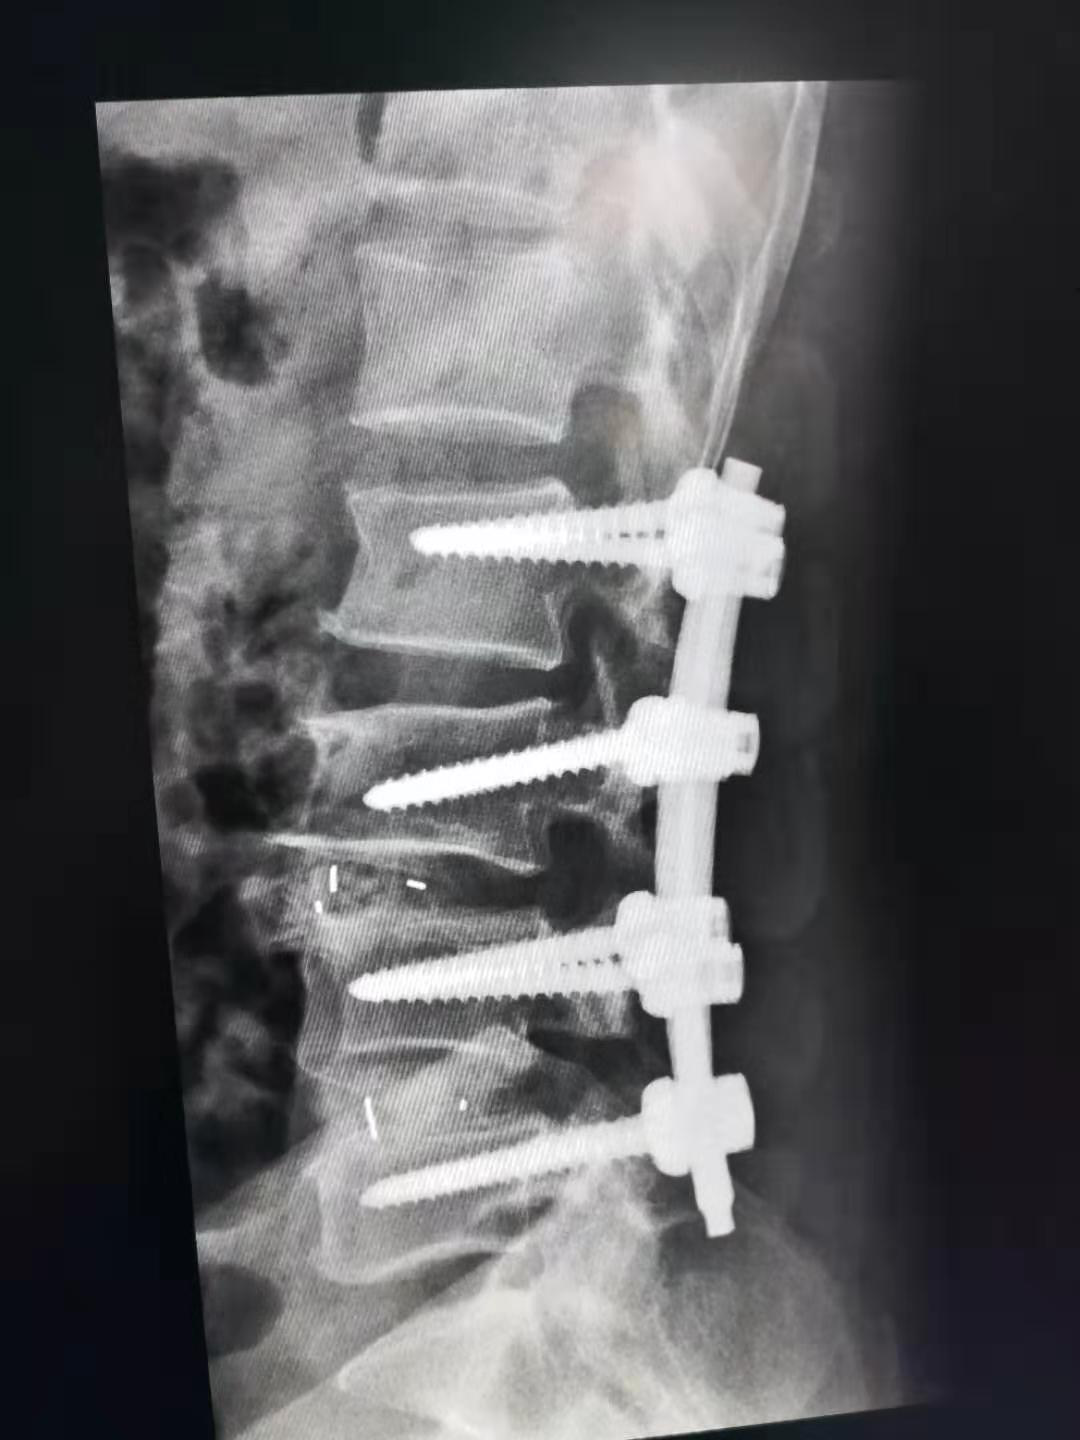

经过完善的术前准备后,为患者在全麻下行腰椎L2-L5侧凸矫形、L3/4 L4/5经椎间孔入路椎间盘切除椎体间植骨融合、L2/3后路关节突关节成形植骨融合L2-L5RSS内固定术,手术由侯卫涛副主任医师、常乐主治医师配合,历时3个半小时,顺利完成。

术后患者X片